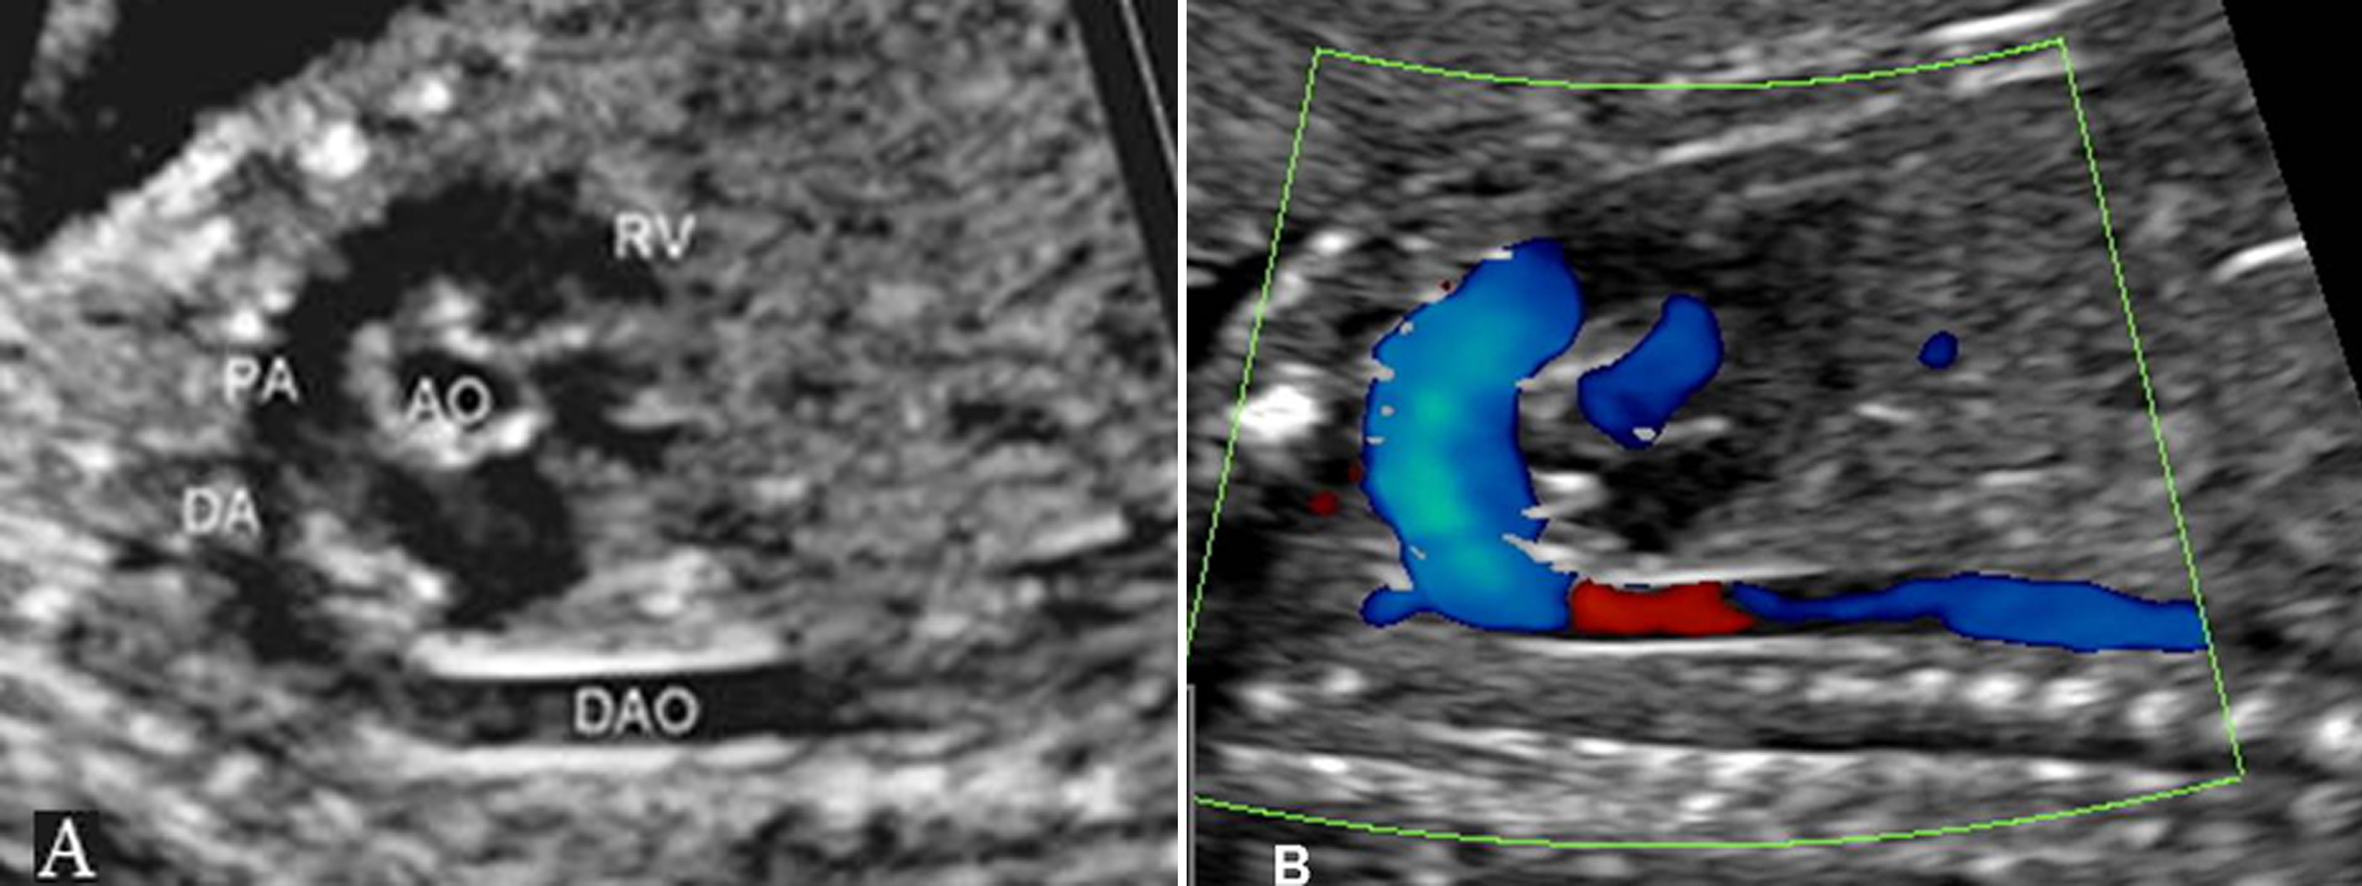

2.肺动脉瓣及PA 显示相对困难,有报道认为胎儿PA的血流显示率不足一半,并且血流速度最快的部位在动脉导管处。PA的频谱显示为非对称性的三角形,上升速度大于下降速度(图3、图4)。

图4 右室流出道切面观(A)及血流(B)

由于胎肺血管没有形成正常的充盈状态,RVO流出的血液绝大多数经DA进入降主动脉,PA的阻力明显大于AO。在AO和PA的起始部,AO的血流速度明显大于PA,速度比为1.3:1,而在PA远端,由于较大的DA两端压差而使其内部的血流速度达到140cm/s。胎儿出生后,随着呼吸的开始和肺的充气,肺循环阻力迅速下降,尤其是在胎儿出生6小时以后,肺充气的面积迅速扩大,肺循环阻力下降尤为明显,但血流速度一直小于AO。